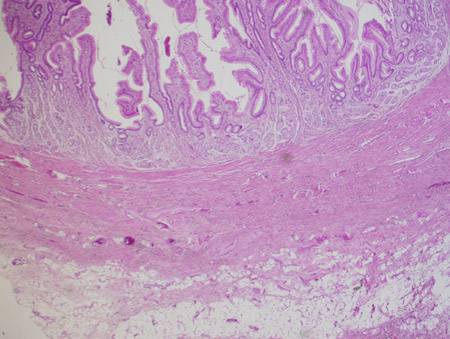

[Figure caption and citation for the preceding image starts]: Gastric submucosal lipoma. A nodule of mature adipose tissue is present subjacent to gastric mucosa. Haematoxylin and eosin, 20x magnificationFrom the collection of Dr Kimberly Moore Dalal and Dr Steven D. DeMartini; used with permission [Citation ends].